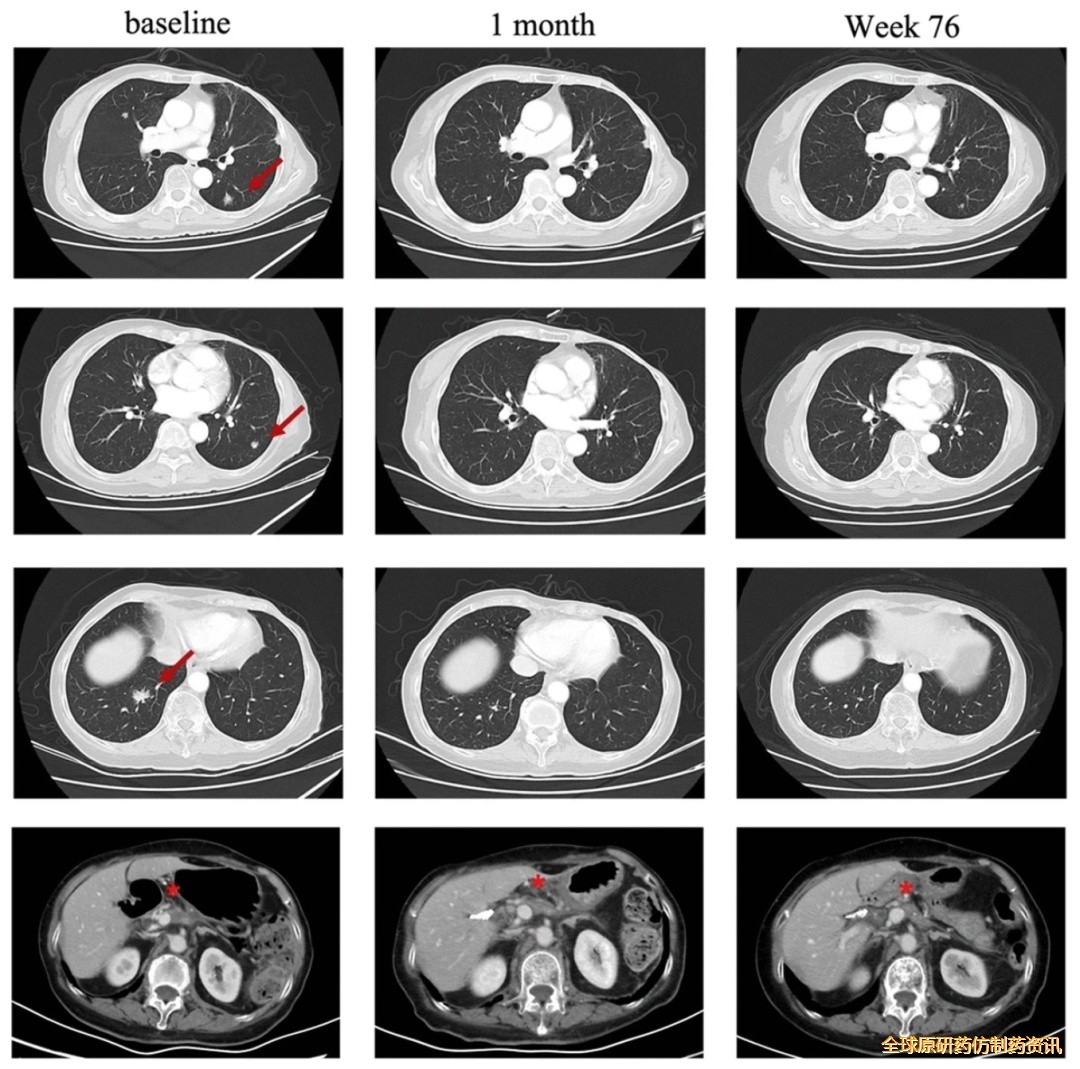

一项应用CT041(针对CLDN18.2阳性实体瘤的自体CAR-T候选产品)治疗胰腺癌的临床研究,曾报道过一个振奋案例。该患者是一位75岁pT2N0期胰腺癌患者,既往接受手术联合S-1单药化疗后疗效不佳,出现肺部肿瘤进展,基于其CLDN18.2表达水平为3+/60%,遂成功入组临床试验。

结果显示:CT041治疗第4周,患者达到部分缓解(PR);后续肺转移靶病灶完全消失,进一步达到完全缓解(CR),截至2023年7月最后一次随访,肿瘤控制情况持续良好。

▼该患者在CT041治疗前后,肺部病变的放射学评估

▲图源“BMC”,版权归原作者所有,如无意中侵犯了知识产权,请联系我们删除